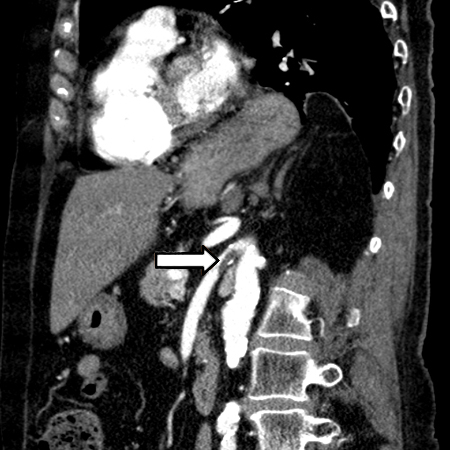

Considere uma angiotomografia precoce em um paciente com dor abdominal e acidose láctica.[8] A angiotomografia substituiu a angiografia convencional como prática padrão para avaliação da vasculatura mesentérica e diagnóstico de isquemia mesentérica aguda.[30] Ela pode ser usada no diagnóstico de uma isquemia mesentérica não oclusiva (IMNO).[43] A angiotomografia também pode fornecer informações para ajudar a decidir sobre a modalidade do tratamento, como o reparo endovascular.

[Figure caption and citation for the preceding image starts]: Angiotomografia: trombo agudo da artéria mesentérica superiorDo acervo da Dra. Jennifer Holder-Murray; usado com permissão [Citation ends].